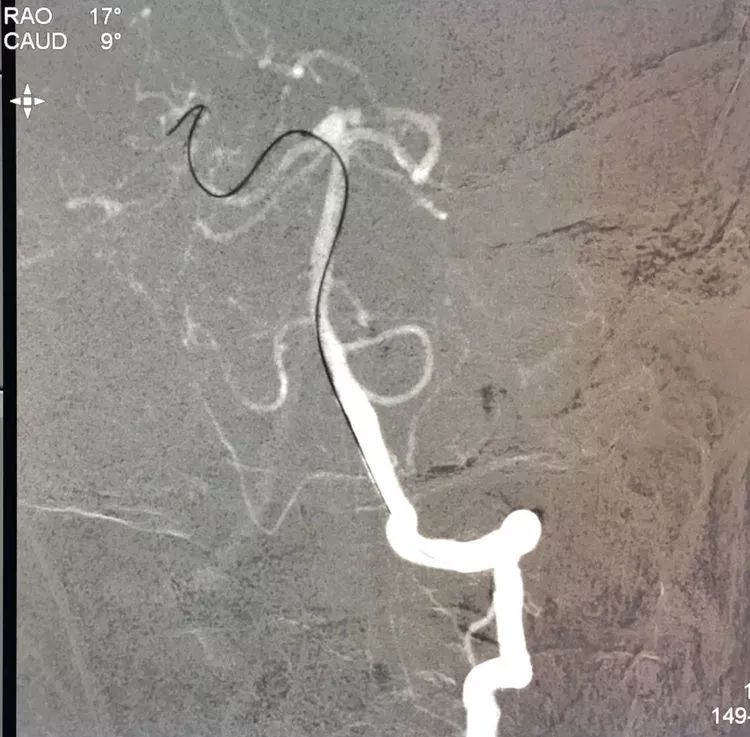

左椎动脉工作位路图

Sychro14微导丝携Headway21支架导管经左椎动脉-基底动脉进入右侧PCA,因瘤颈主要累及右侧PCA,故计划支架跨基底动脉顶端动脉瘤释放于右侧PCA-基底动脉内。

Echelon10(直头)微导管用Sychro14微导丝引入瘤腔内。